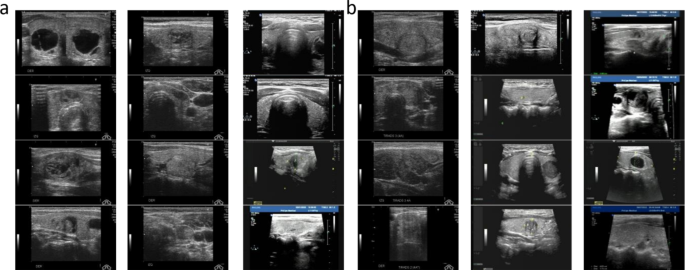

The external test set collected from Hanzhong Central Hospital consisted of 410 malignant and 192 benign nodules, totaling 602 ultrasound images. This is in contrast to the internal dataset sourced from the publicly accessible DDTI database, which included 622 malignant and 624 benign cases for training, and 292 malignant and 286 benign cases for validation. The external dataset did not participate in the initial model training but served as an external validation set to assess the model’s generalization ability and practical application value. The flow of the data collection and analysis is illustrated in the CONSORT diagram (Fig. 5), and the dataset breakdown is shown in Fig. 6. It is noteworthy that this retrospective study was conducted in accordance with the Declaration of Helsinki and was approved by the Ethics Committee of Hanzhong Central Hospital (Approval No.2024(18)), and waived the requirement for the written informed consent of the patients, because the selected clinical and imaging data in this retrospective study would not affect the prognosis and privacy of the patients.

Display of the data set. Among them, 2a means Malignant and 2b means benign